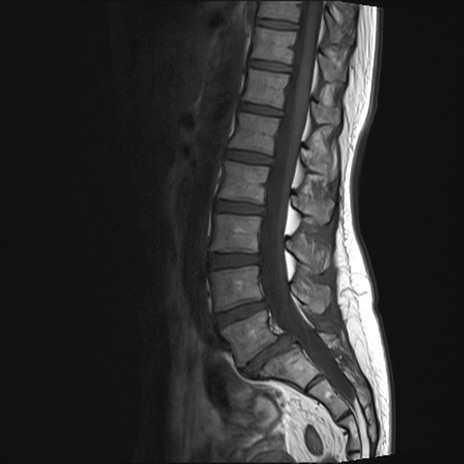

腰椎MRI

T2WI(横断像)

T2WI(矢状断像)